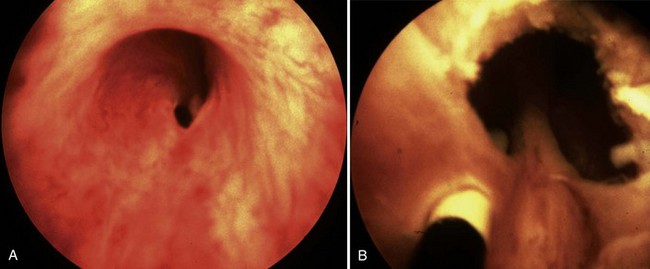

Today a number of successful surgical techniques are available to disrupt or destroy posterior urethral valves including hooks, balloon catheters, and valvulotomes (Deane et al, 1988; Kolicinski, 1988; Cromie et al, 1994; Chandna et al, 1996; Chertin et al, 2002). One of the more common methods uses the Whitaker hook. This instrument looks like a crochet hook and has been used successfully to cut valves either blindly or with fluoroscopic control (Whitaker and Sherwood, 1986). New, smaller pediatric cystoscopes with improved optics are favored today because of the ability to perform the procedure under direct vision. A bugbee electrode or a pediatric resectoscope with a hook or cold knife can be used to incise the valves (Fig. 126–8). A number of authors report using a cystoscope and laser to disrupt valves (Ehrlich and Shanberg, 1988; Biewald and Schier, 1992; Gholdoian et al, 1998). Although most surgeons incise the valves from a retrograde position viewed through the urethra, others have found that an antegrade approach through a vesicostomy or suprapubic puncture of the bladder is helpful (Zaontz and Firlit, 1985).

Figure 126–8 Cystoscopic photographs made from the distal urethra show the posterior urethral valves before ablation (A) and after ablation (B). The ureteral catheter has been passed through a perforation in the valve leaflet.

Originally surgeons attempted to completely resect the valves. This practice produced frequent complications from urethral stricture resulting from electrosurgical and instrument damage to the urethra. Modern appropriately sized cystoscopic equipment and limited use of electrosurgery have reduced the incidence of urethral injury to 5% (Nijman and Scholtmeyer, 1991). Today the goal is not to remove the valves but to incise them so that they are not suspended across the urethra obstructing urine flow. Well-placed incisions can disrupt their integrity and allow the valves to lie freely along the walls of the urethra when the child voids. The exact point of incision can vary; some surgeons prefer the 12 o’clock position, others prefer incisions at 4 and 8 o’clock, and others all three. Although most valves are quite thin and do not bleed at surgery, it is sometimes preferable to leave a catheter in place for 24 hours after incision. The valve remnants involute after incision, and there is often no evidence of them on later cystoscopic examination.